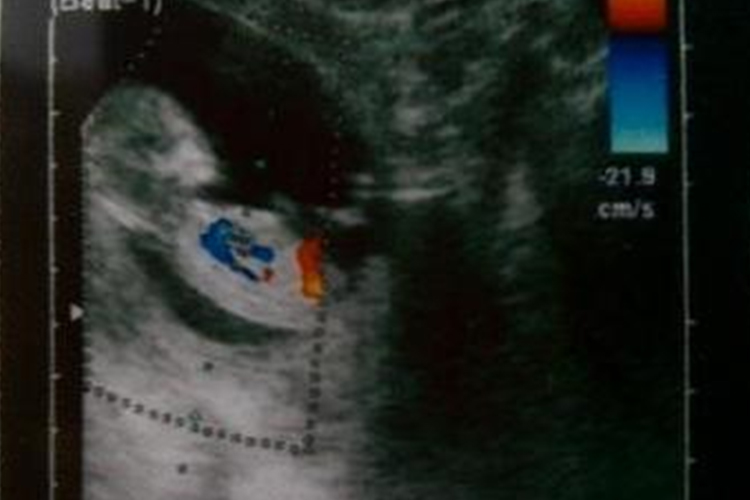

超音波檢查(通常在8-16週間進行)

- 評估胎兒數量、大小、心跳、羊水量等